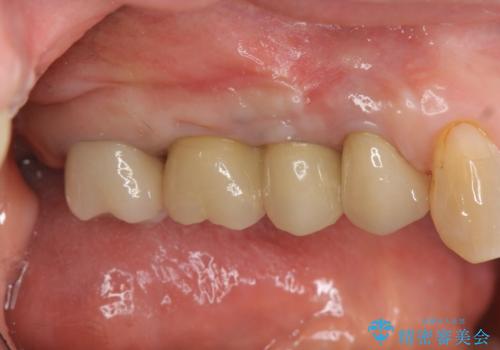

過大な咬合力で破折した奥歯 インプラント治療で咬合機能の回復